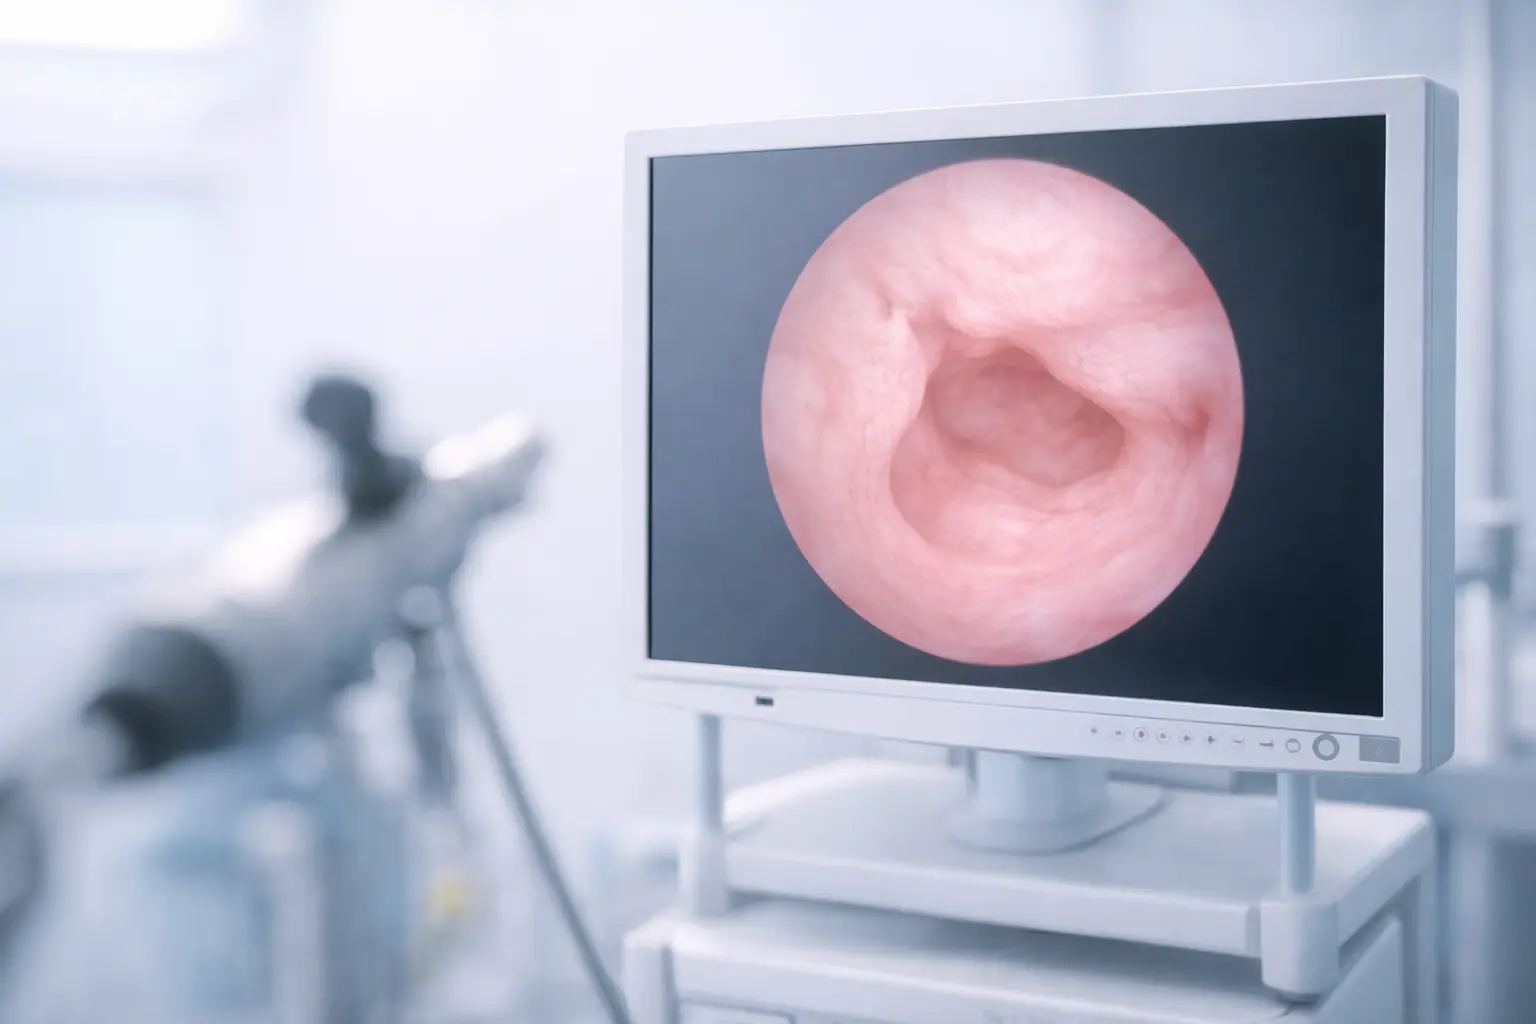

Hysteroscopy (direct visualisation of the uterine cavity using a thin camera)

Hysteroscopy is often the gold standard for diagnosing and treating uterine polyps in the same procedure.

Hysteroscopic polypectomy: using a thin camera inserted through the cervix, polyps can be removed under direct vision without any cuts or stitches.